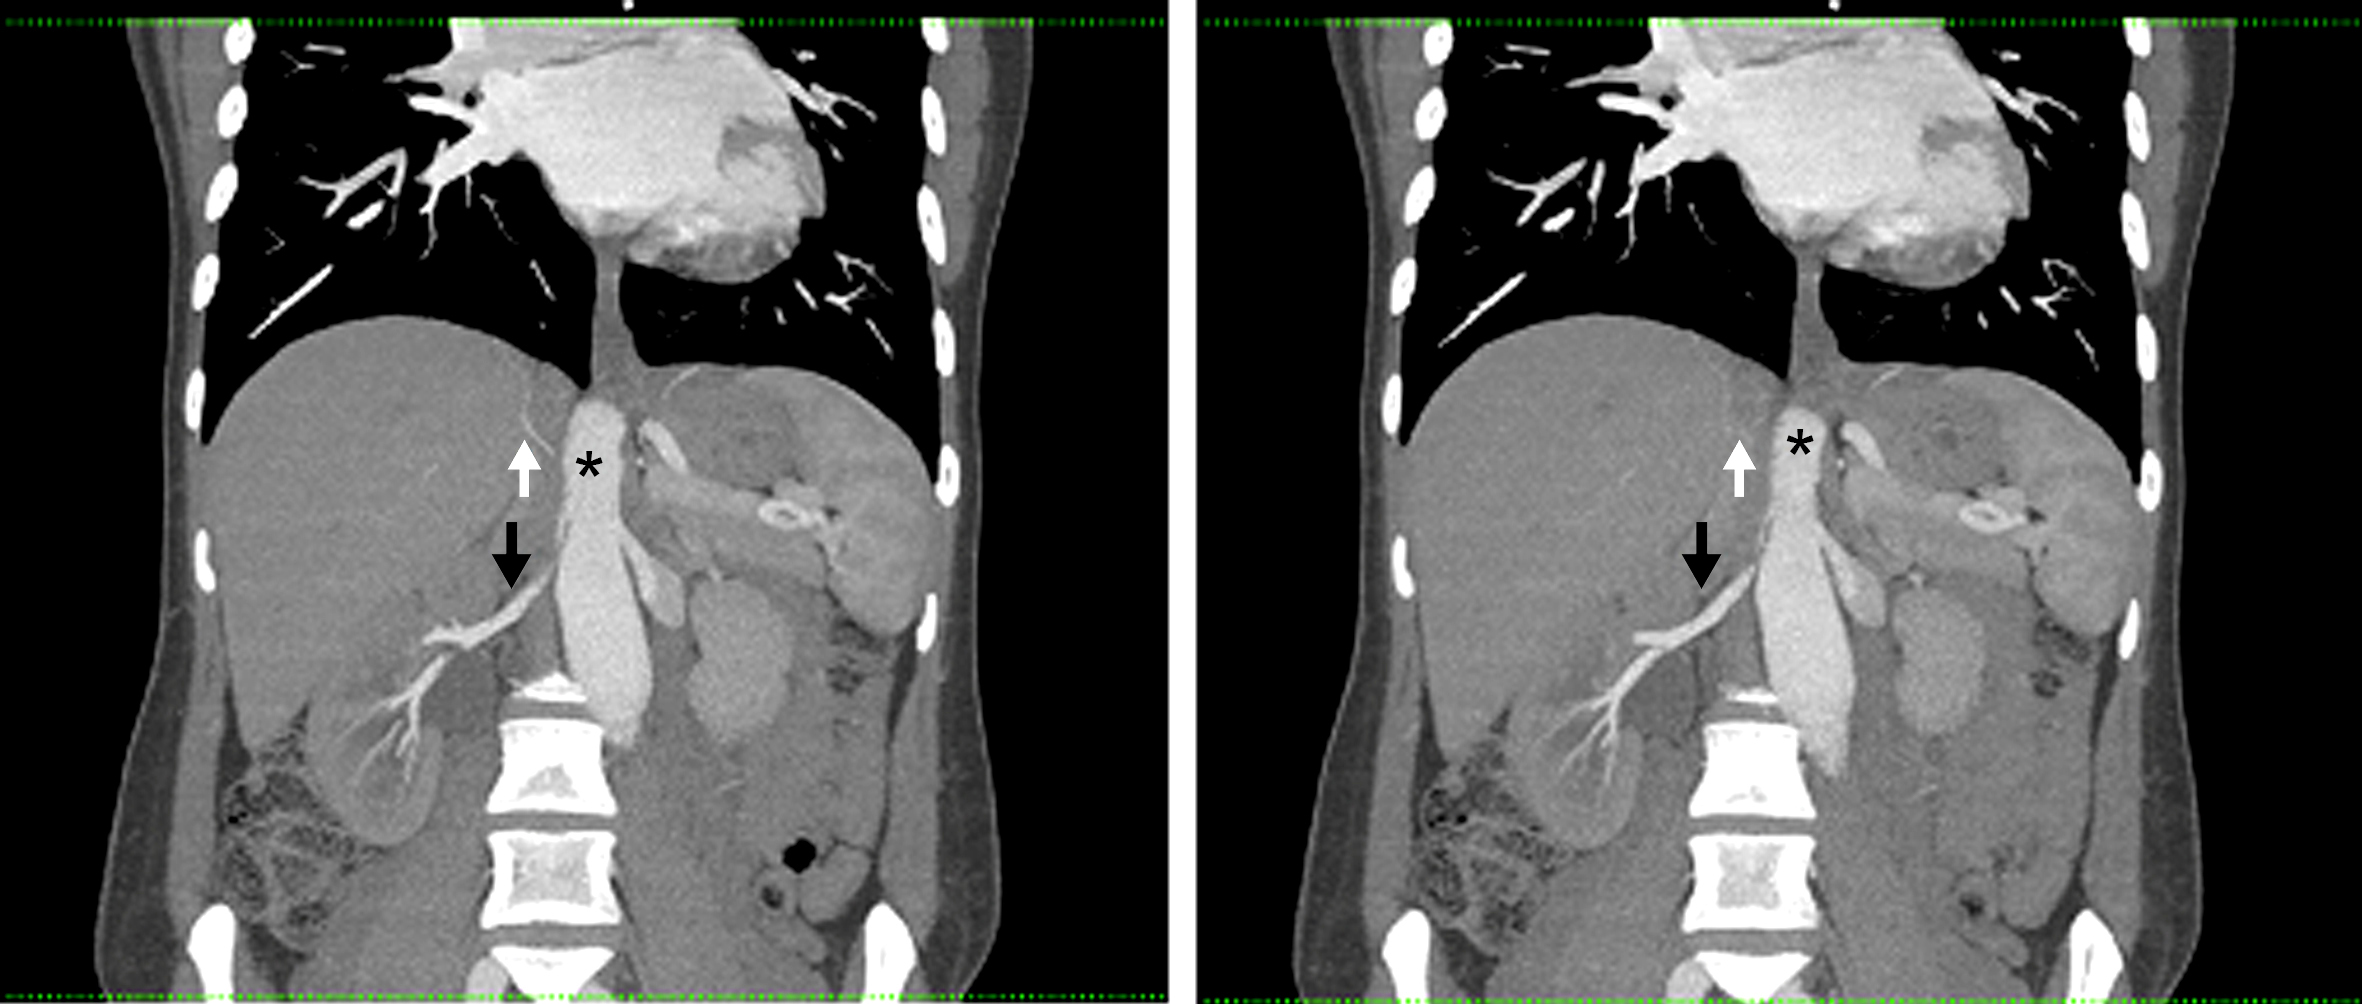

La arteria renal derecha es única, se encuentra permeable, y presenta franca disminución de su calibre y trayecto “verticalizado” en su sector proximal, transcurriendo entre la aorta abdominal y la crura diafragmática ipsilateral en su segmento inicial. Distalmente la arteria renal derecha presenta calibre normal, de aprox. 6 mm de diámetro. Así mismo se observa realce asimétrico de ambos riñones tras la administración de medio de contraste i/v, evidenciándose menor captación del mismo en forma difusa a derecha (nefrograma tardío) en comparación con el riñón contralateral, lo cual traduce hipoperfusión renal. (Figs. 1 y 2)

El tronco celíaco y la arteria mesentérica superior se encuentran permeables y de calibre habitual. Se identifica un origen alto de las ramas viscerales de la aorta abdominal, a saber, el tronco celíaco a la altura del espacio discal T11-T12, la arteria mesentérica superior a nivel del cuerpo vertebral de T12, la arteria renal derecha a nivel del espacio T12-L1 y de la arteria renal izquierda a nivel del margen superior de cuerpo de L1. (Fig. 3)

Por último destacamos la presencia de un útero grávido con feto en su interior, antecedente que ya conocíamos. Los hallazgos descritos son compatibles con el planteo de Síndrome de atrapamiento de la arteria renal derecha por la crura diafragmática.

Figura 2

Angiografía de Aorta por TC Proyección de máxima intensidad. Cortes coronales. (*) Aorta abdominal, (flecha blanca) Crura diafragmática derecha, (flecha negra) Arteria renal derecha.